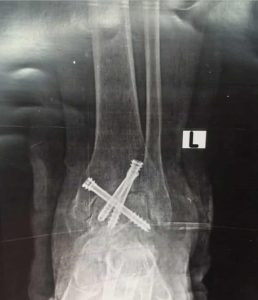

قامت الوحدة بإجراء جراحة لمريض ستيني يعاني من آلام مزمنه وتشوه وتيبس مفصل الكاحل الأيسر وعدم القدرة على المشي بصورة طبيعية حيث تم عمل سمكرة كاملة لمفصل الكاحل لإنهاء معاناة المريض المزمنه عن طريق منظار الكاحل والتدخل الدقيق المحدود والتثبيت بثلاثة مسامير ثنائية الضغط وتمت الجراحة كاملة من خلال جروح بسيطه لا تتعدى واحد سنتيمتر بدون فتح جراحي تقليدي والمريض بصحة جيدة وفي مرحلة التعافي والعلاج